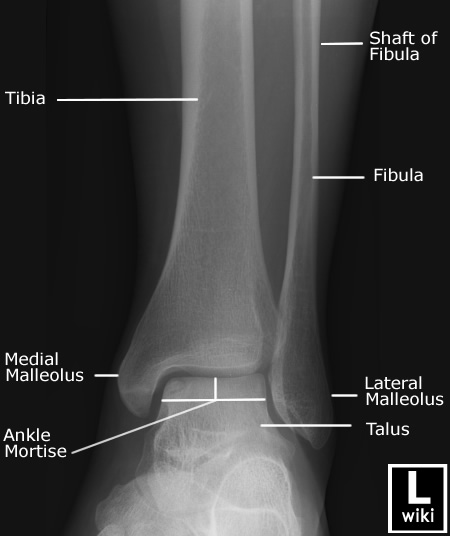

| [Anatomy] Ankle(발목) (0) | 2024.01.25 |